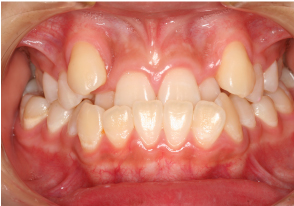

叢生(スペース不足のため、歯がデコボコに並んでいる)

●治療担当:増岡

BEFORE

スペース不足のため、デコボコに並んでおり、奥歯の咬み合わせ位置にも問題があります。

AFTER

咬み合わせ位置の改善と、理想的な歯並びが再現できました。